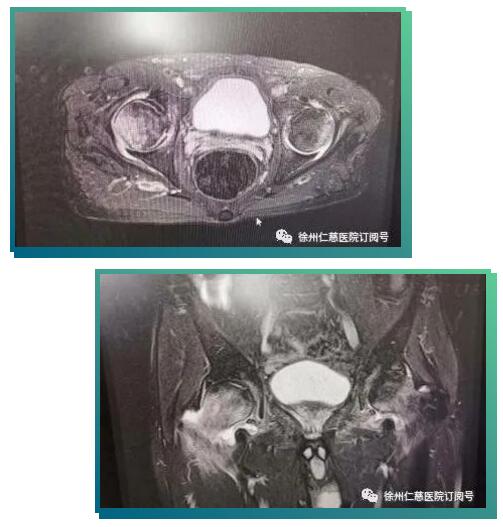

接诊的关节科邱东新副主任医师询问病史,给李师傅做了仔细的检查,磁共振片显示患者双侧股骨头坏死,同时患有腰椎间盘突出、椎管狭窄、腰椎不稳(这是引起腰痛的原因)。患者的双髋疼痛在当地以为是腰痛引发,来必威官方首页官网betway后,邱医师经过仔细检查,发现髋部疼痛其实是由股骨头坏死引起的;目前患者的股骨头坏死尚处于早期阶段,还能采取保髋治疗;如果直接置换关节,不仅创伤大,且因患者年纪不大,还要考虑未来假体翻修的问题,综合考虑之后,邱医生决定采用骨科机器人辅助完成保髋手术。

完善的术前准备后,6月17日,邱东新、徐猛、杨沛霖手术团队给患者进行了机器人辅助下双侧股骨头坏死髓芯减压术,骨科机器人在主刀医生的操纵下精准地“定位聚焦”病灶,设计好进针点,通过骨科机器人机械臂的引导,将导针分毫不差地均匀打入股骨头坏死病灶,达到病灶彻底减压的目的。手术全过程无切口,仅有三个极小的钉道口。